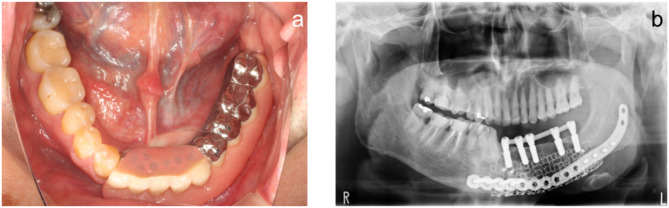

Background: A case of postoperative mandibular defects was successfully managed using an intraoral scanner and computer-aided design/computer-aided manufacturing (CAD/CAM) technology, facilitating jaw reconstruction and functional restoration with implants for a critical mandibular defect.

Case presentation: The intraoral scanner was used to scan the maxilla and mandible, and occlusal scans were acquired. The obtained data were imported to CAD/CAM software to design the virtual teeth. Digital Imaging and Communications in Medicine data of preoperative cone-beam computed tomography images were converted to three-dimensional (3D) data using specialized software to examine the mandibular bone volume and modify the jawbone morphology. All data were superimposed on the implant simulation software, and jawbone morphology was modified considering the implant placement position. The finalized jawbone 3D data were printed using a 3D printer. Then, a titanium mesh tray was fabricated on the 3D printed model. Subsequently, iliac cancellous bone grafting using a titanium mesh tray and implant treatment were performed.

Conclusions: The application of digital technology helped visualize the final image of the treatment result and collaborate closely with the oral surgeon from the pre-reconstruction stage. This technique allows mandible reconstruction after considering the implant placement based on the ideal prosthesis.